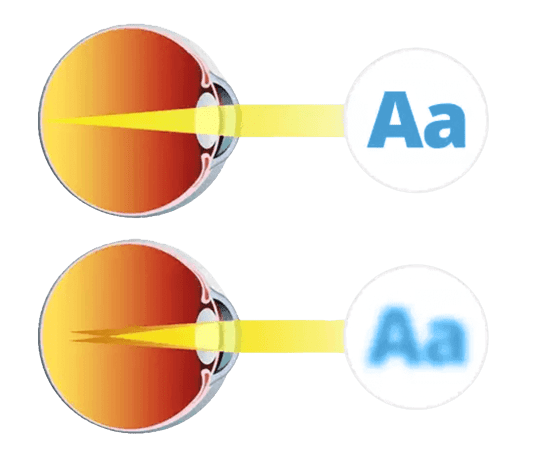

¡La causa principal de una mala visión es el mal funcionamento los músculos de los ojos!!

- El sistema muscular enfoca los ojos de tal manera que la imagen que pasa a través del cristalino se proyecta en la retina.

- El trastorno del músculo ocular da como resultado una compresión insuficiente o excesiva del globo ocular.

- El cristalino está deformado y el foco está distorsionado, por lo que ya no puedes ver con claridad.